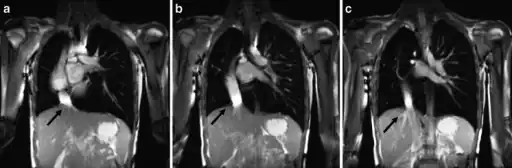

a-c) Scimitar syndrome in a young male- Breath-hold coronal 2-D steady-state free precession demonstrates the anomalous partial pulmonary venous return